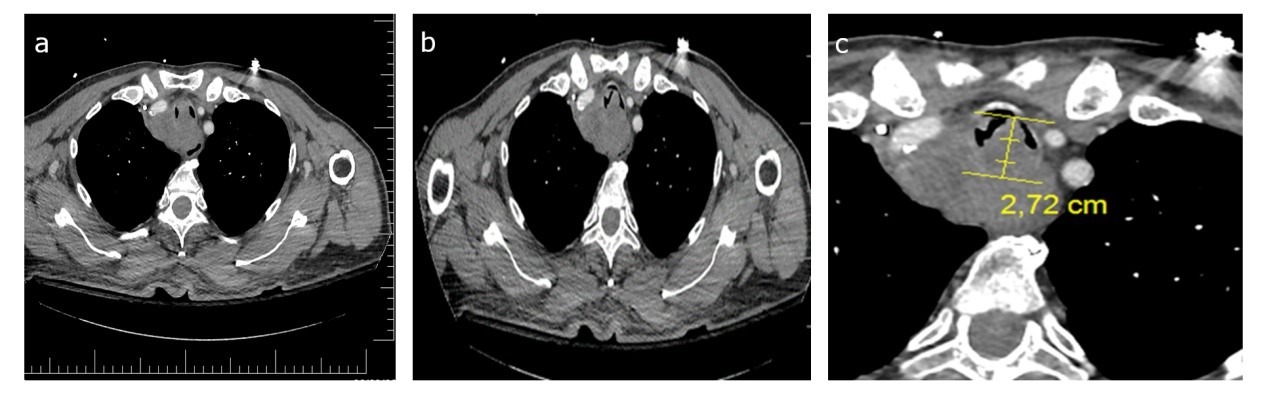

Due to the refractory nature of the presumed asthma exacerbation in an elderly patient with no prior history of asthma, the emergency physician consulted with the intensive care and pulmonology teams and decided to pursue additional imaging. An urgent computed tomography (CT) scan of the neck and chest with pulmonary angiography was performed, which revealed a mass in the upper mediastinum invading the posterior wall of the trachea causing significant obstruction (Fig 2). Additionally, a right lung infiltrate with radial projections affecting the lateral aspect of the middle lobe was noted, suspicious for malignant spread. No pulmonary embolism was identified.

Figure 2. Computed tomography images of the thorax (axial views): Sequential cuts demonstrating a) and b) mass arising from the posterior wall of the trachea, and c) mass measurement showing maximal diameter of 2.72 cm causing significant airway obstruction.